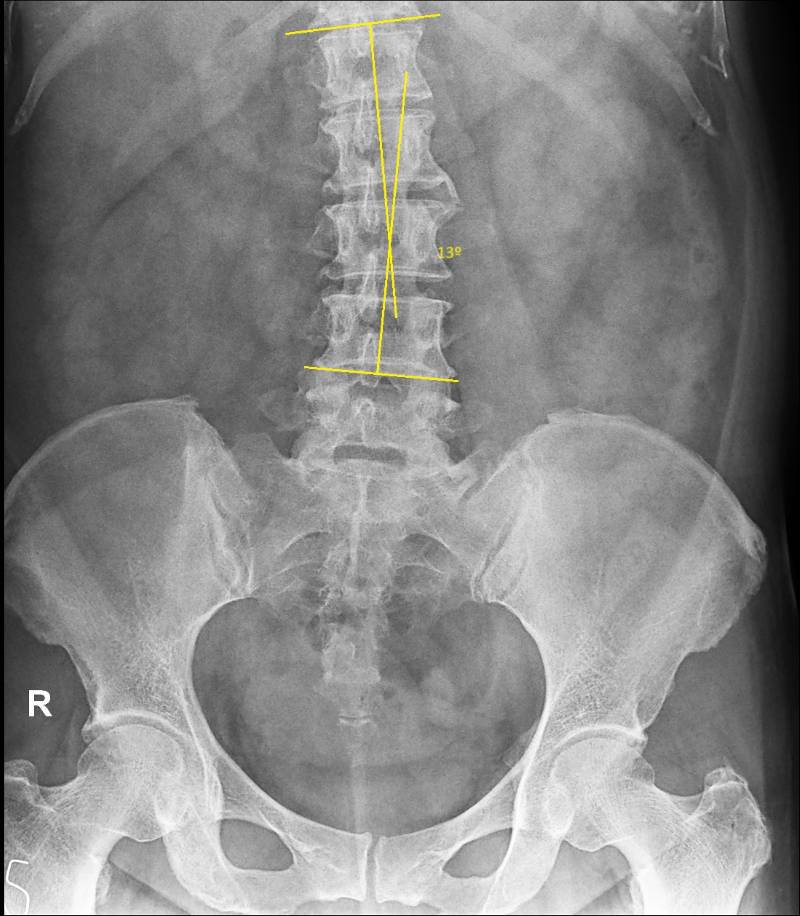

Mild lumbar levoscoliosis

Cobb’s angle 13º